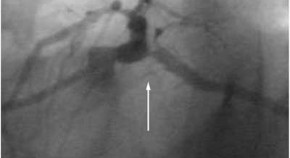

The primary objective of invasive treatment strategies for multivessel coronary artery disease is complete anatomical revascularization. As objective evidence of ischemia can be provided by a functional assessment based on fractional flow reserve, the focus of contemporary treatment could shift from anatomical to functional revascularization. In this Perspectives article, the authors summarize the data that supports contemporary functional revascularization and its applicability to real-world practice.